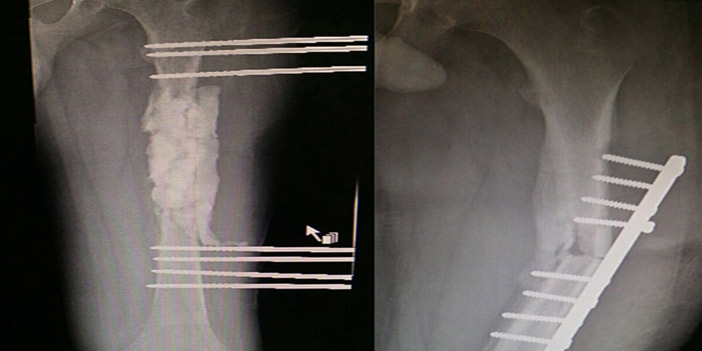

والذي أضاف أنه فور وصول المريض لقسم الطوارئ بالمستشفى تم إخضاعه للفحوصات المخبرية والأشعة، حيث تبيّن وجود أخطاء متعددة نتجت عن العلاج السابق الأمر الذي أدى إلى عدم التئام الكسر وحدوث التهاب بالعظم وخروج المسامير الخاصة بالتثبيت بالإضافة إلى ملاحظة ميلان في عظمة الفخذ.

وأشار الدكتور إلى أنه تم العمل على تعديل الميلان في العظم ووضع كرات مضاد حيوي مكان الالتهاب مع إبقاء الجرح مفتوحاً لتسهيل خروج الصديد الكثيف، إذ تمت تغطية الجرح بتقنية غيار الشفط (Vacuum Dressing) الحديثة والتي تساعد على شفط الصديد من الجرح بالضغط السالب والشفط المستمر، وبعد 3 أيام تم تحويل المريض للعمليات مرة أخرى لتنظيف الجرح والتأكد من نظافة الجرح تم وضع جبيرة (مخلوطة بالمضاد الحيوي لمنع عودة الالتهاب) مكان العظم المفقود مع إبقاء العضلات والأنسجة حول الكسر سليمة لتحفيز نمو غشاء عظم جديد حول مكان العظم المفقود (Induced membrane technique) ولتسهيل التئامه مستقبلاً بتقنية (Mosquetet) الحديثة. واستطرد الدكتور حديثه قائلاً إنه بعد إبقاء المريض 40 يوماً في المستشفى وإخضاعه لبرنامج علاج طبيعي ومتابعته الدقيقة بالمضادات الحيوية وتحاليل الدم تم إجراء أشعة والتي أكدت وجود تحسن ملحوظ وزوال الالتهاب ولله الحمد، حيث تقرَّر إجراء العملية الثالثة الأخيرة. موضحاً أن العملية الأخيرة تكونت من عدة خطوات: منها إزالة الأسياخ الخارجية والجبيرة من مكان الكسر مع الحرص على إبقاء الغشاء الجديد سليماً.

وقال الدكتور إنه تم أيضاً زراعة العظم المسامي حول الكسر ثم إغلاق الغشاء العظمي الجديد وتثبيته بصفيحة طويلة تم تجهيزها من قبل العملية خصيصاً لتلائم الطول المناسب وتثبيتها بتقنية المسامير المقفلة التي تساعد على تثبيت الصفيحة أكثر من المسامير العادية ثم إغلاق الجرح.